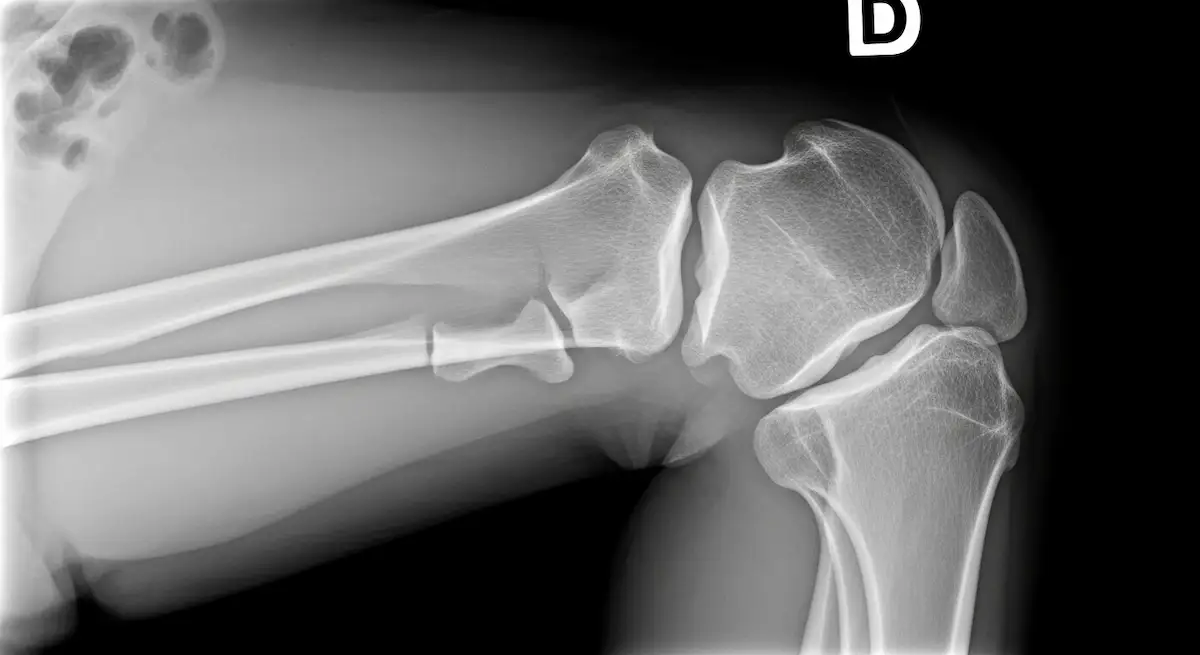

A fratura do planalto tibial envolve a parte superior da tíbia, região que forma a base da articulação do joelho.

O planalto tibial possui dois platôs, medial e lateral, ambos recobertos por cartilagem.

- Radiografias em duas incidências para confirmar o traço.

- Tomografia para mapear fragmentos, depressões e planejar a cirurgia.

Classificação

Os padrões variam de linhas de fratura sem desvio até depressões do platô e quebras que atingem os dois lados.

Quanto maior o desvio, a depressão da superfície e o número de fragmentos, maior a complexidade e a chance de cirurgia.